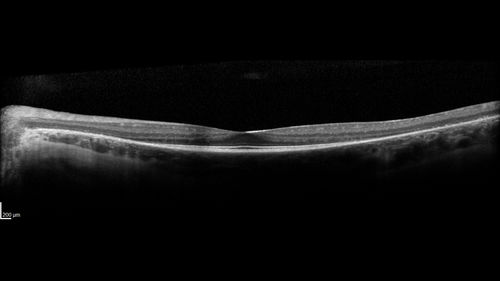

Retinitis Pigmentosa - Simplex - 16 year old female good vision

Difficulty with night vision

No family history

VA 20/25 OD, 20/16 OS

Negative for RPE65